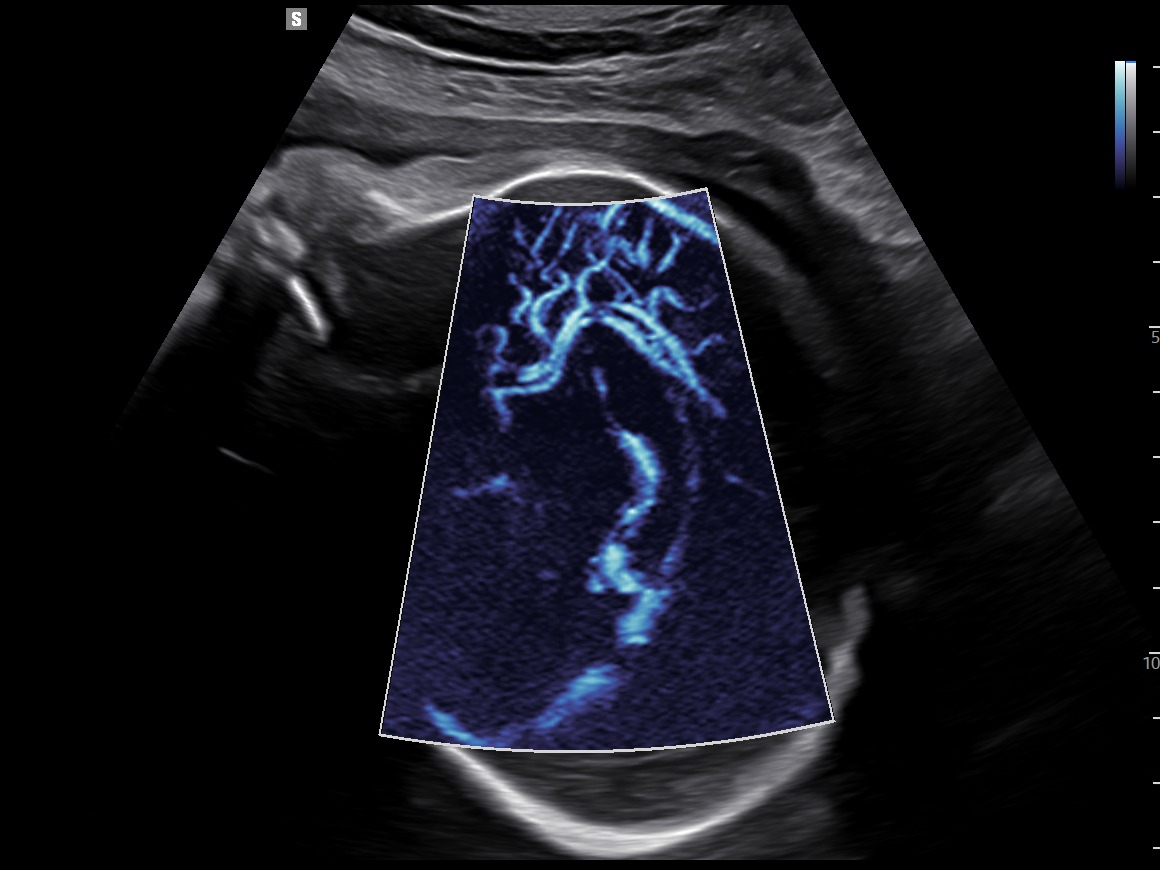

MV-Flow™ offre une nouvelle alternative au Doppler Énergie pour visualiser les flux lents et la microvascularisation des structures. Les hautes cadences images et les filtres d’imagerie avancés permettent au MV-Flow™ de coder le mouvement des hématies en s’abstenant des artefacts de l’imagerie B et ainsi améliorer la résolution spatiale.

LumiFlow™ est un codage de visualisation avec un effet tridimensionnel qui permet d’étudier l’architecture des vaisseaux, de manière intuitive.